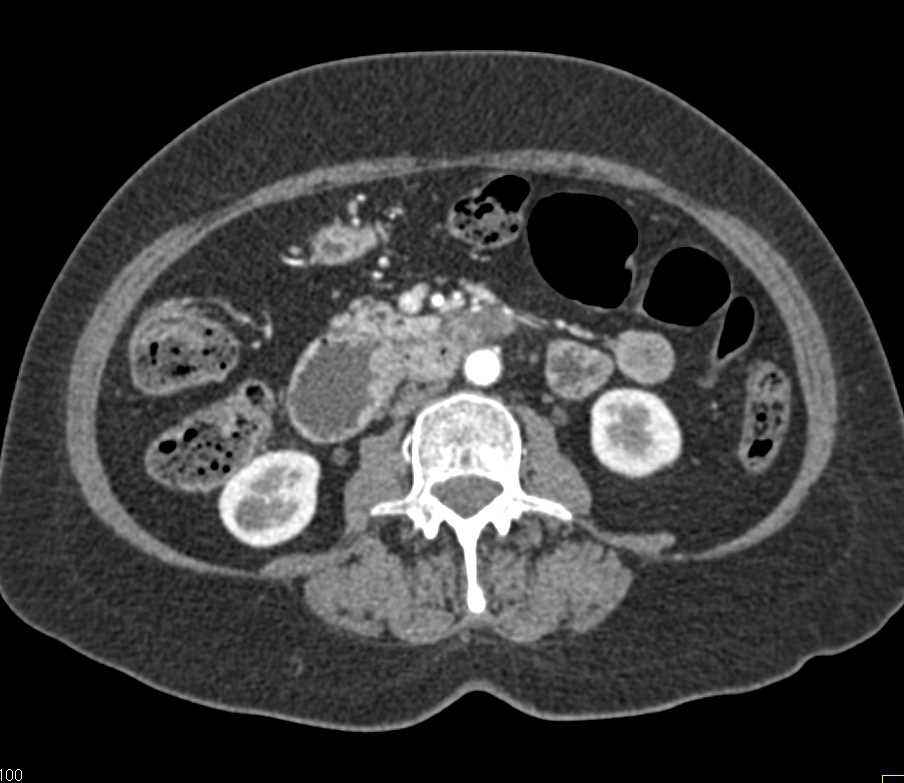

Duodenal Carcinoma with Obstruction